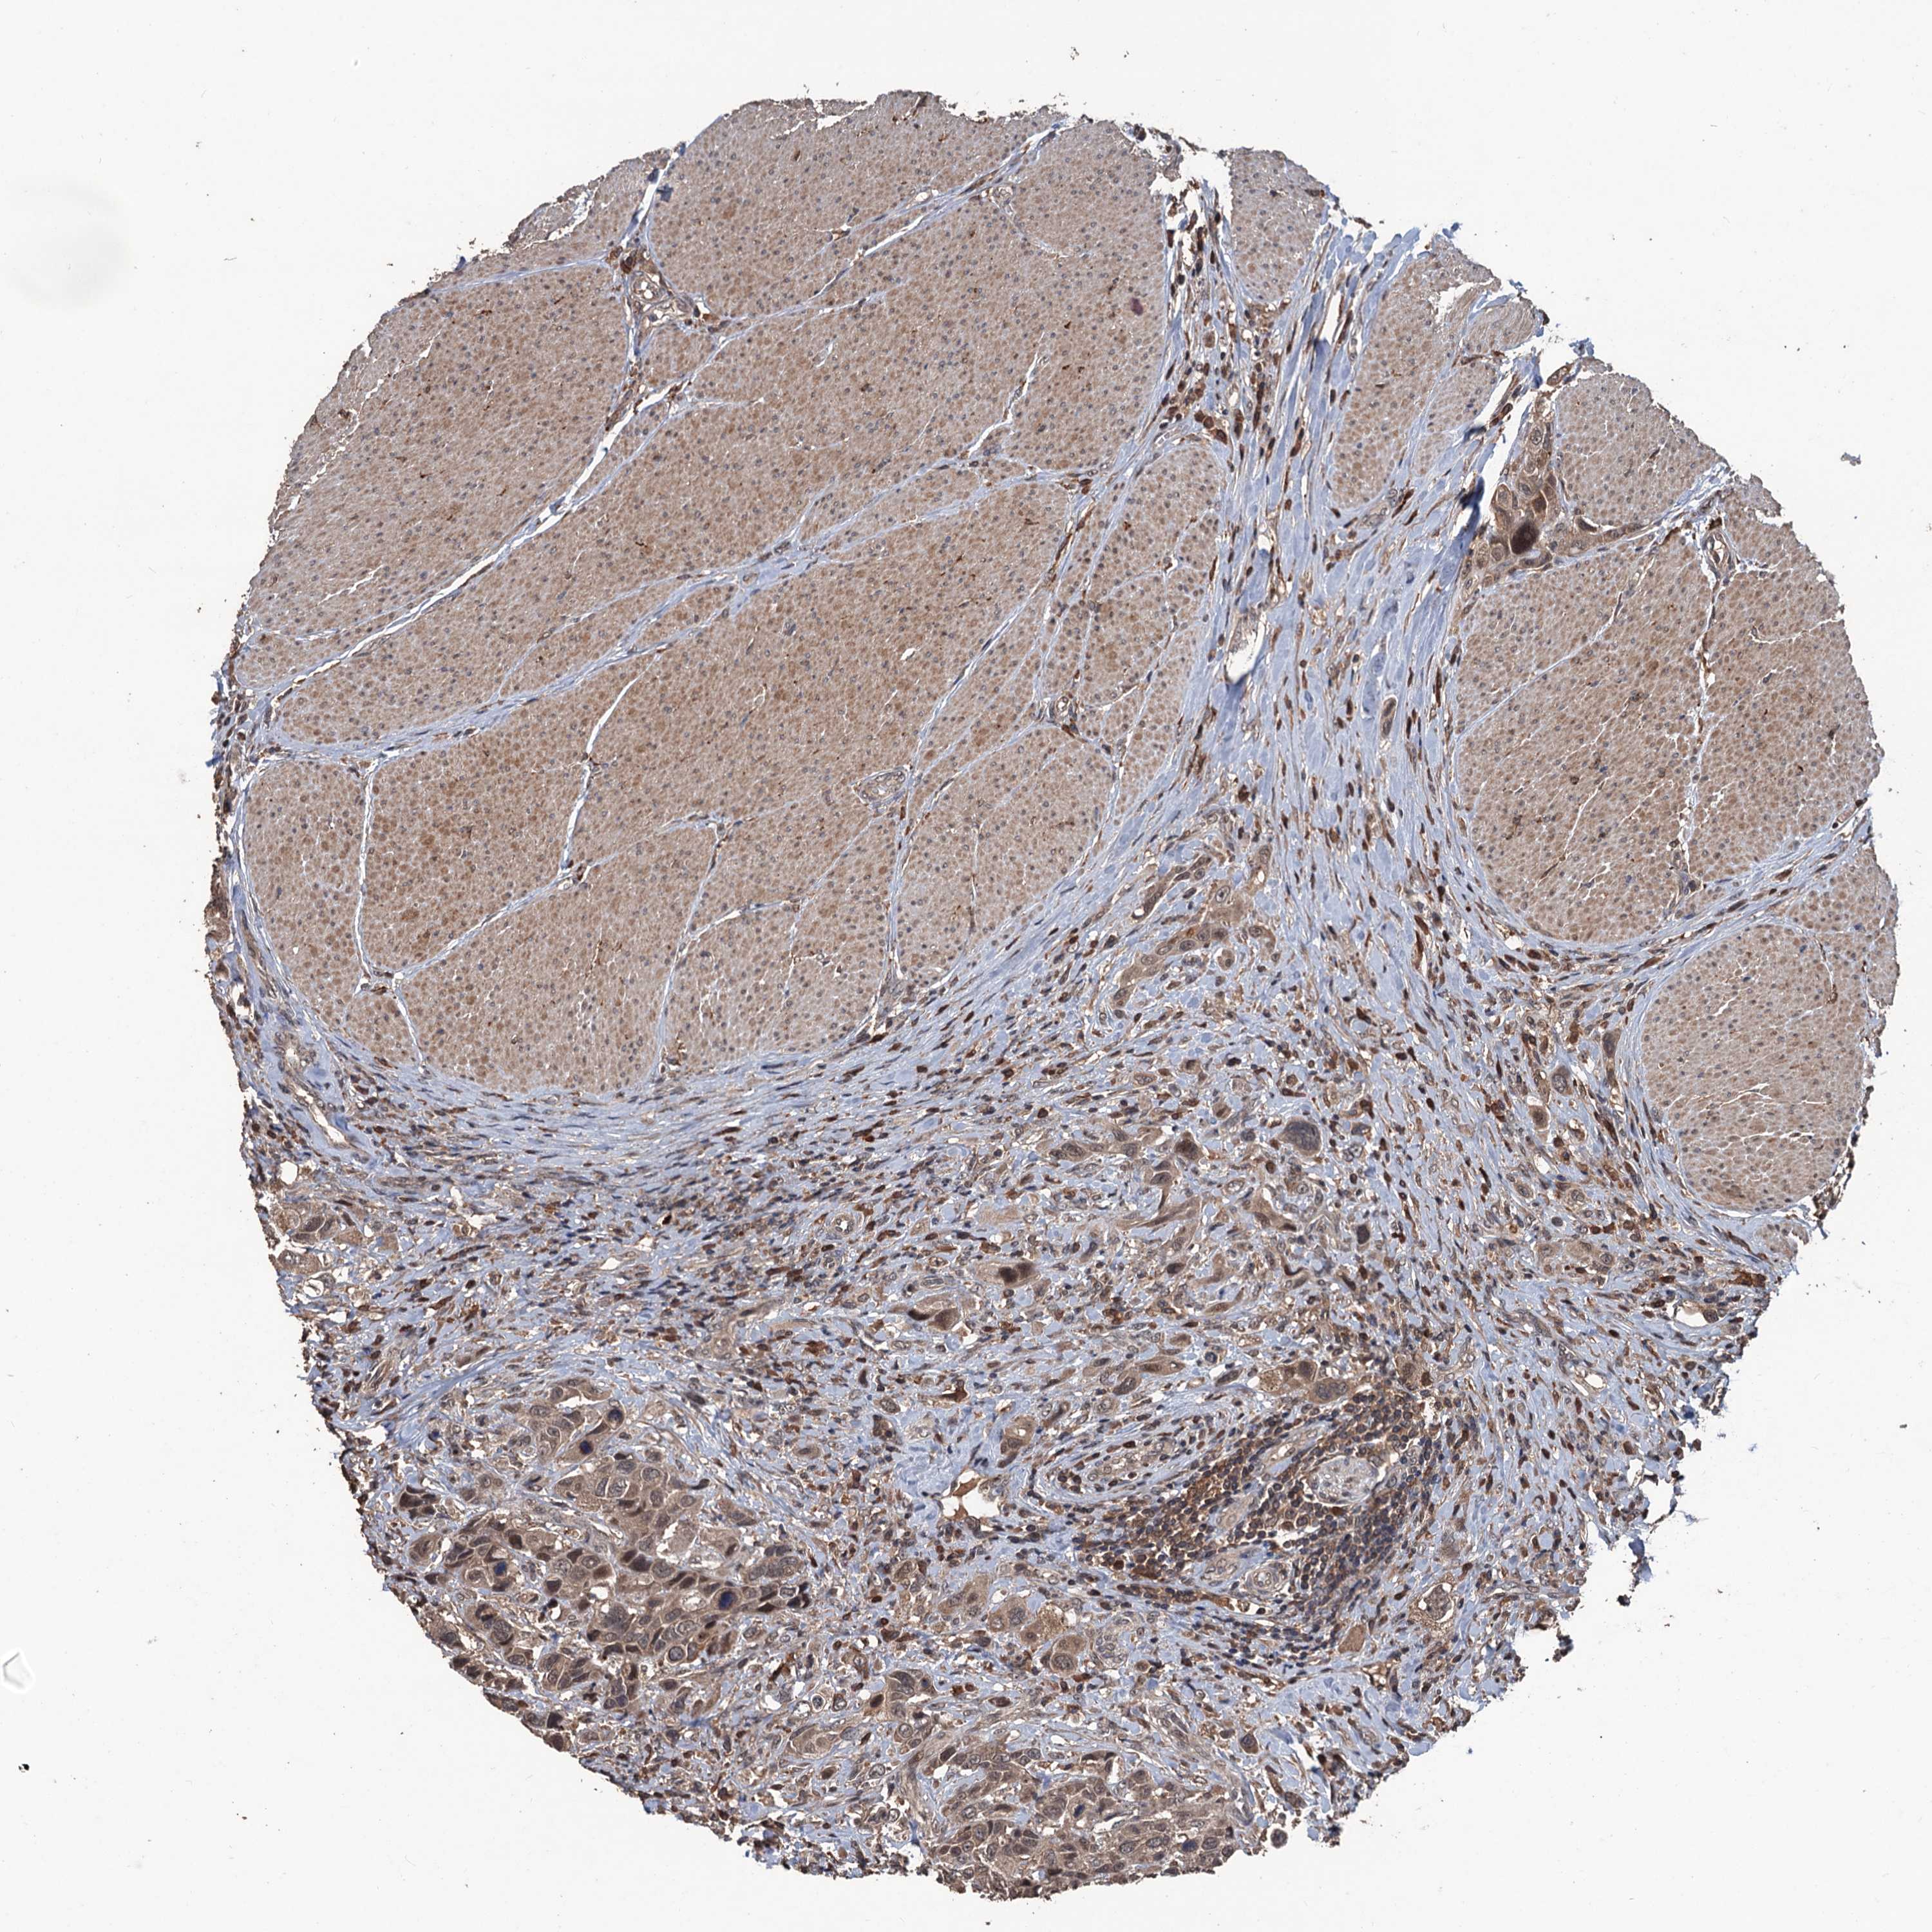

UROTHELIAL CANCER - Protein expressioni

A mouse-over function shows sample information and annotation data. Click on an image to view it in a full screen mode. Samples can be filtered based on level of antibody staining by selecting one or several of the following categories: high, medium, low and not detected. The assay and annotation is described here.

Antibody stainingi

Antibody staining in the annotated cell types in the current human tissue is reported as not detected, low, medium, or high, based on conventional immunohistochemistry profiling in selected tissues. This score is based on the combination of the staining intensity and fraction of stained cells.

Each image is clickable and will lead to virtual microscopy that enables deeper exploration of all samples and also displays staining intensity scores, fraction scores and subcellular localization as well as patient and tissue information for each sample.

Antibody HPA039843

Staining

High

Medium

Low

Not detected

Intensity

Strong

Moderate

Weak

Negative

Quantity

>75%

75%-25%

<25%

None

Location

Nuclear

Cytoplasmic/membranous

Cytoplasmic/membranous,nuclear

Urothelial carcinoma, High grade

Urothelial carcinoma, Low grade